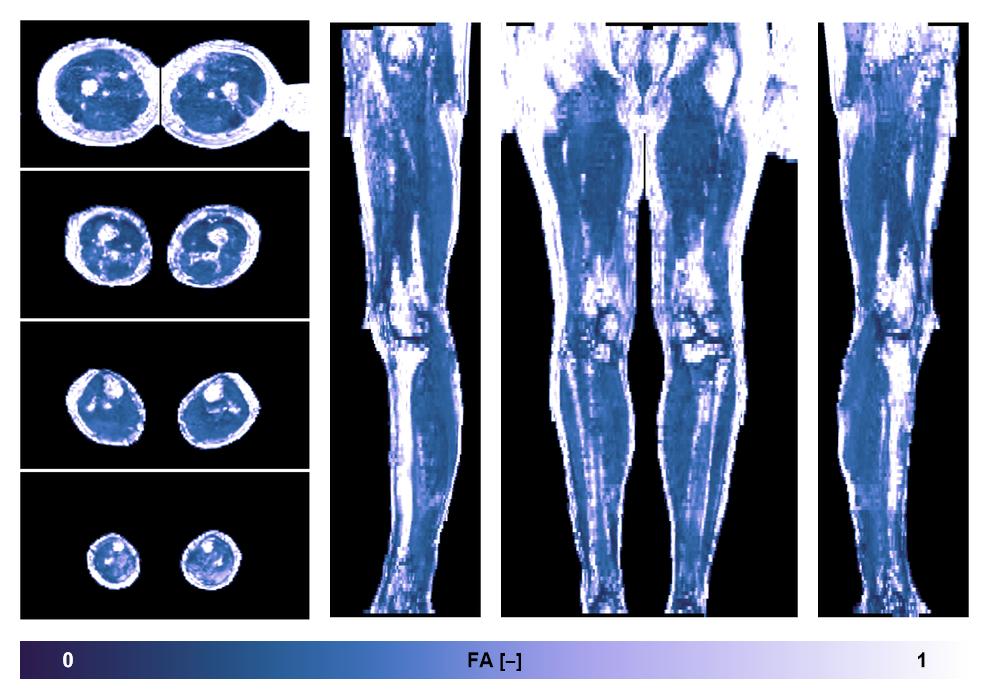

• Fractional anisotropy

IVIM corrected whole leg muscle fractional anisotropy obtained from diffusion tensor imaging.